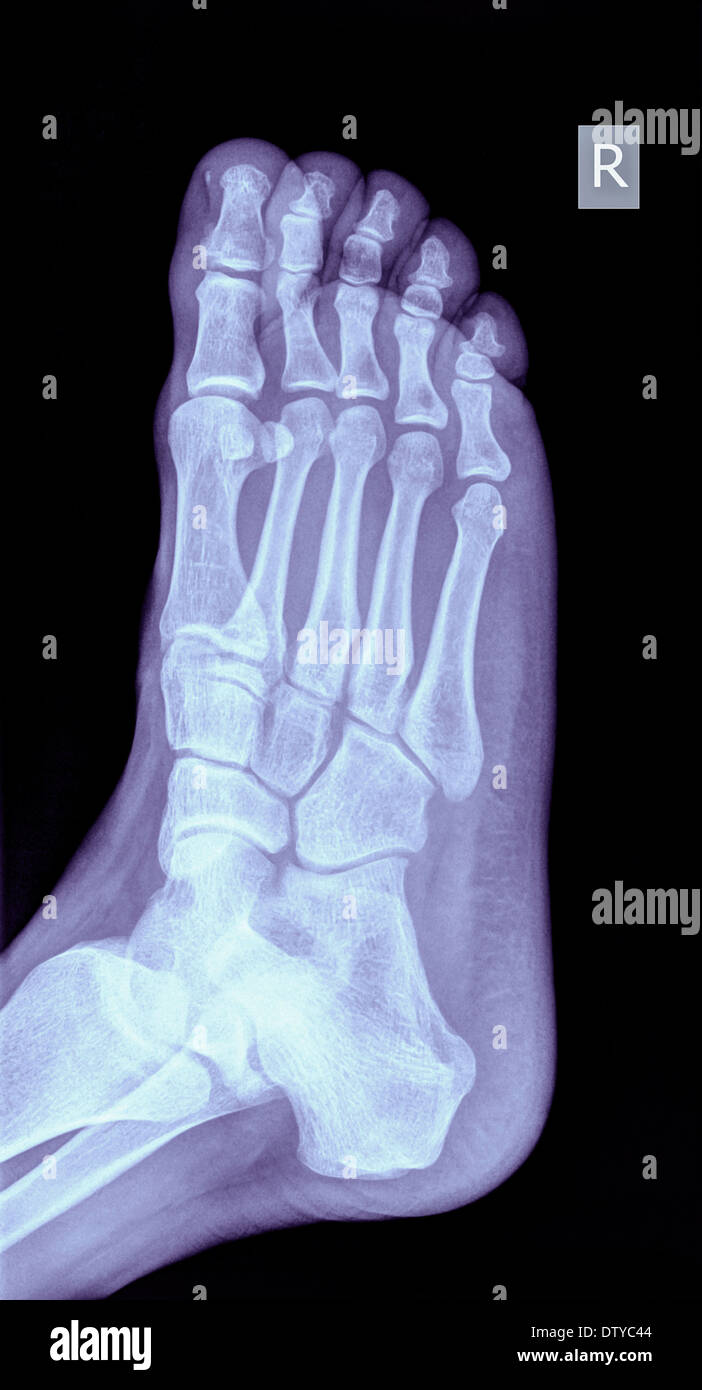

Raggi X Di Un Piede Che Mostra Una Frattura Nel 5 Metatarsalia Di 31 Anni Maschio Foto Stock Alamy

Piede A Raggi X Quinto Metatarso Frattura Di Piccolo Osso Piede Per Frattura Foto Premium